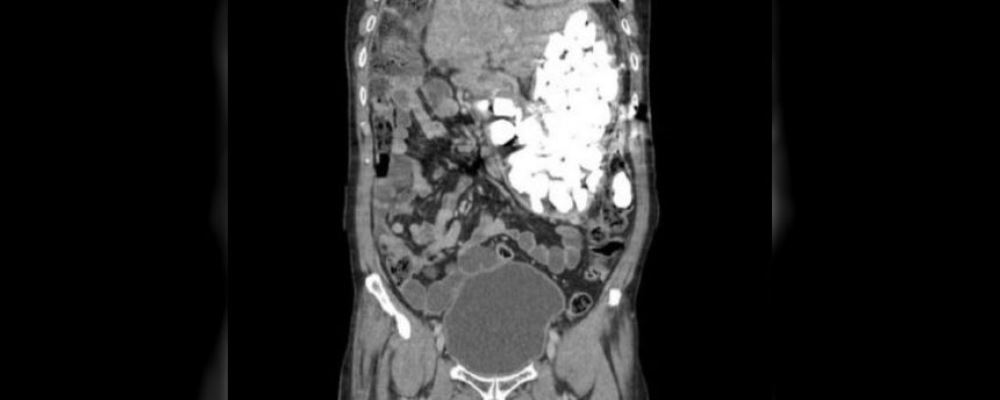

Al descubrir mediante un escáner los objetos en el estómago del hombre, explicó el médico, este reveló que los había estado ingiriendo durante la última semana debido a severos ataques de ansiedad, pese que llevaba a cabo un tratamiento con pastillas para controlar su comportamiento.

En el hospital intentaron extraer los objetos desde el estómago mediante una gastroscopía, insertando un tubo delgado en el estómago a través de la boca, pero este procedimiento falló debido a la gran cantidad de metales presentes en el organismo.